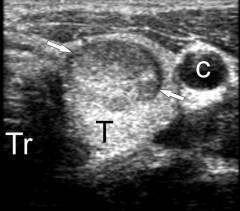

6.       УЗИ щитовидной железы

УЗИ щитовидной железы назначается всем пациентам при обнаружении узла, увеличении или уменьшении объема щитовидной железы. В ходе процедуры определяют количество, размер и точное расположение узлов, а также состояние самой железы.

Признаки узлов щитовидной железы на УЗИ

• Контуры железы не ровные – выпуклость на границе органа в месте образования узла.

• Структура железы не однородная – узел может поглощать ультразвук лучше или хуже окружающей ткани.

• Анэхогенные образования – узлы в щитовидной железе не способные отражать ультразвук. На экране выглядят как темные пятна. Это могут быть кисты с четкими контурами и жидкостью внутри или коллоидные узлы.

• Гипоэхогенные образования – структура плохо отражающая УЗ-волны. Это могут быть кисты, скопления сосудов, отечные участки, пропитанные жидкостью. На экране монитора они выглядят как темные пятна.

• Гиперэхогенные образования – плотный узел, содержащий мало жидкости. Он хорошо отражает ультразвук и выглядит как светлое пятно. Это может быть аденома, участки отложения кальция, папиллярный рак, который не инкапсулировался.

Различные виды узлов щитовидной железы на УЗИ

2. Киста

• анэхогенный округлый узел – темное округлое образование с четкими контурами

• гиперэхогенный светлый тонкий ободок – плотная соединительная капсула кисты

• отсутствие сосудов внутри узла